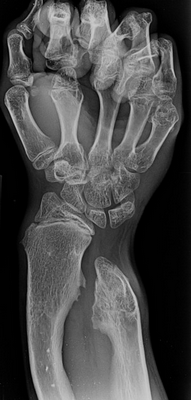

Основным методом диагностики является рентген в 2-х проекциях. На снимках визуализируется только костная часть опухоли в виде новообразования с четкими границами и соединенного тонкой ножкой или толстым основанием с материнской костью. Также наблюдается истончение кортикального слоя кости, а сама остеохондрома часто имеет вид «цветной капусты» из-за участков обызвествлений в хрящевой шапочке.

Сам хрящевой колпачок на рентгеновских снимках не отображается, хотя его величина важна для определения вероятности озлокачествления. В норме толщина хрящевого слоя не должна превышать 1,5—2 см. Поэтому в спорных случаях, а также детям с высокой скоростью роста остеохондромы нередко дополнительно назначается проведение КТ или МРТ. В результате удается не только точно визуализировать хрящевую шапочку, измерить ее параметры, но и определить расположение сосудисто-нервного пучка, а также оценить состояние плечевого, локтевого сустава или кисти. Это дает возможность разработать оптимальную тактику лечения.